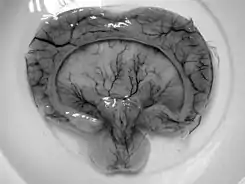

Holoprosencefalia alobar, producto de una madre de 19 años en Tailandia con diabetes gestacional.[1]

• Holoprosencefalia alobar es el tipo más grave, en la cual el cerebro no logra separarse y se asocia generalmente a anomalías faciales severas (fusión de los ojos, anomalías del tabique nasal.)[4]